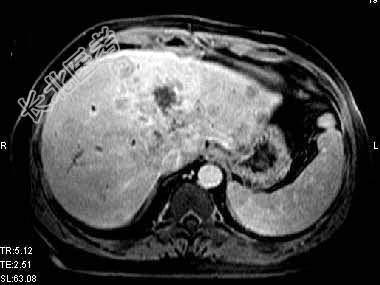

- 单项选择题根据所提供的图像,最可能的诊断是 ( )

A、肝转移癌

B、肝细胞癌

C、肝胆管细胞癌

D、肝血管瘤

E、以上都不是